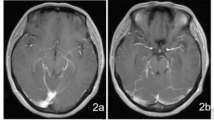

Of the three widely used traditional microbiological tests, CSF CrAg was positive in all the 27 references CM cases. CSF culture and CSF India ink staining failed to detect 8 (29.6%) and 6 (24.0%, 6/25; India ink staining was not performed in 2 culture positive cases) CM cases, respectively (Fig. 2A). NTS was able to detect 23 (85.2%) CM cases, and 2 of those 23 cases could not be confirmed by cryptococcal PCR (Fig. 2B). When all the diagnostic tests were considered, 14 CM cases were tested positive by all of those tests (Fig. 2C). Consequently, the sensitivities of CSF CrAg, CSF culture, CSF India ink staining, CSF cryptococcal PCR and CSF NTS for diagnosing were 100% (95%CI: 87.5 − 100%), 70.4% (95%CI: 51.5 − 84.1%), 76.0% (95%CI: 56.6 − 88.5%), 77.8% (59.2 − 89.4%) and 85.2% (95%CI: 67.5 − 94.1%), respectively (Table 2). Patients with higher CSF CrAg titers seemed to have higher cryptococcal sequencing reads reported by CSF NTS (p = 0.089; Fig. 3), and there was moderated correlation between cryptococcal PCR Ct value and NTS cryptococcal sequencing reads (Spearman’s r = 0.57; p = 0.002; Fig. 3). The pairwise comparison of the sensitivities between different tests were shown in Supplemental Table 5. There was no statistical significance of the sensitivity between CSF CrAg and CSF NTS for diagnosing CM among HIV-infected patients (p = 0.134; Supplemental Table 5). All the tests had high specificity (100%) that a positive result could confirm a CM case (Table 2).

Venn diagrams of positive results of different methods. Positive results of different methods in 27 cryptococcal meningitis cases, including cryptococcal antigen (CrAg), culture, India ink staining, nanopore targeted sequencing (NTS), polymerase chain reaction (PCR). (A) CrAg, culture, India ink staining. (B) CrAg, NTS, PCR. (C) culture, India ink staining, NTS, PCR.